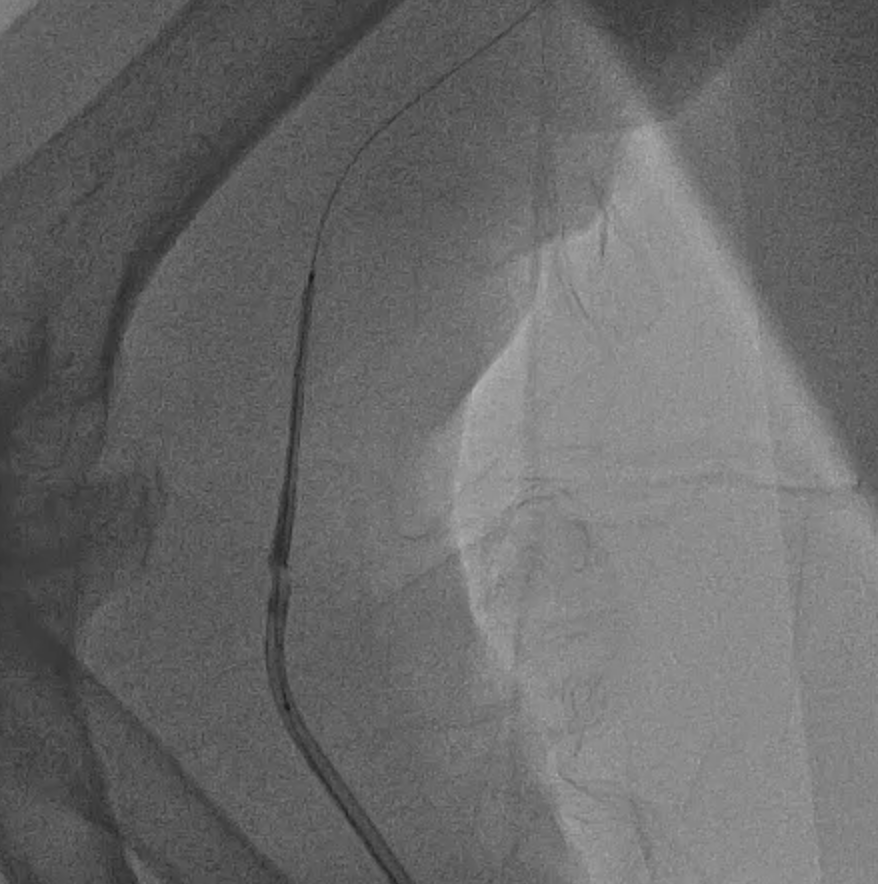

We attempt to pass a 50 mm long stent to cover both lesions, but encountered difficulty due to pRCA calcification. Manipulation with the guiding catheter led to partial stent dislodgement from the balloon.

Then we proceeded to retrieval of the dislodged stent. We pushed the old system back to the aorta and we snared the wire with ENsnare. The proximal portion of the stent was significantly deformed and could not go into the JR4 guiding catheter from femoral side. We tried different methods including using a larger and longer sheath, manipulations to optimise alignment, changing to a different snare but we still failed. At last, we successfully retrieved the stent with the use of biopsy forceps.